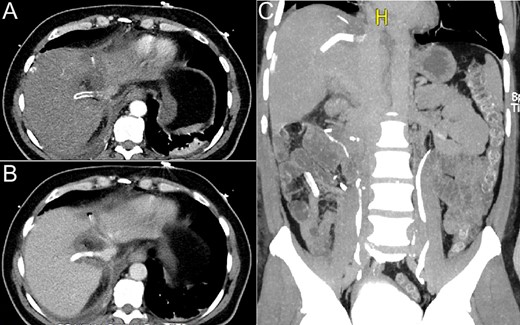

Computed tomography (CT) disclosed a 4.0 × 2.0 cm lesion in Segment 8 involving the entire circumference of the right hepatic vein (which was still partially patent), extending medially to the middle hepatic vein and posteriorly to the retrohepatic inferior vena cava (IVC) (Fig. 1).

(A) and (B) Preoperative CT showing displacement of the tumour and its relationship with the right and middle hepatic veins and the IVC. (C) Schematic drawing of the tumour.